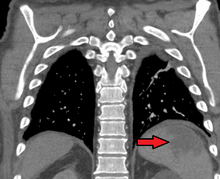

Splenic infarction is a condition in which oxygen supply to the spleen is interrupted, leading to partial or complete infarction (tissue death due to oxygen shortage) in the organ.[1]

Splenic infarction occurs when the splenic artery or one of its branches are occluded, for example by a blood clot. Although it can occur asymptomatically, the typical symptom is severe pain in the left upper quadrant of the abdomen, sometimes radiating to the left shoulder. Fever and chills develop in some cases.[2] It has to be differentiated from other causes of acute abdomen.

An abdominal CT scan is the most commonly used modality to confirm the diagnosis,[2] although abdominal ultrasound can also contribute.[3][4][5]